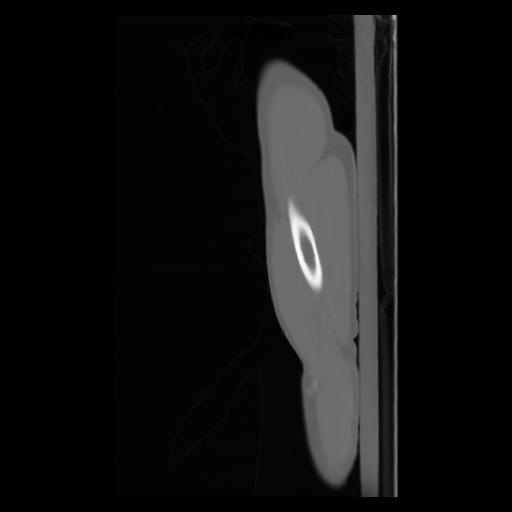

30 CUERPO,CE,Sagittal,3.000,CUERPO,Sagittal,